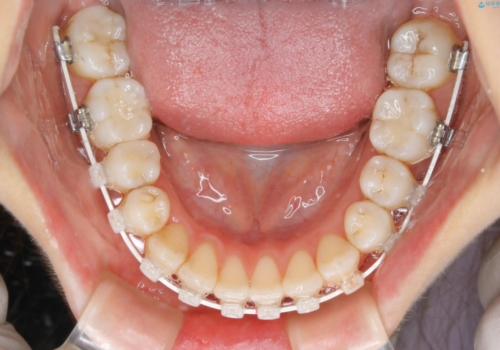

- 矯正装置

- ワイヤー矯正 審美装置

マイクロインプラントについて

インビザライン治療では奥歯の圧下が問題なく行えますが、ワイヤー治療ではマイクロインプラントを使用しなければ奥歯の圧下を行うことが難しいです。